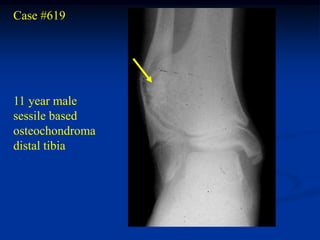

Case #619

11 year male

sessile based

osteochondroma

distal tibia